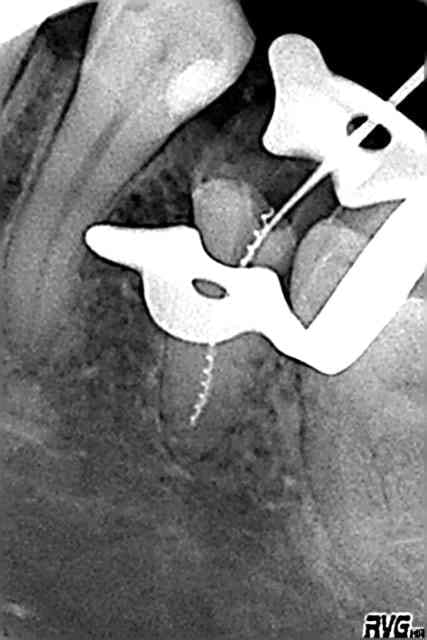

D'apres mon confrere le Dr. Vafancullo; si tu ouvres correctement ta cavité, degages 2 ou 3 mm a la fraise de touati autour de ton protaper, il se pourrait meme que les US à fond les manettes suffisent .

Parce qu'une fois bien accessible dans l'axe; il est qd meme peté tellement haut qu'on croirait un screw-post

ça a pas du te prendre 5 minutes!!!

US et fraise, c'est vraiment pour le cas de depart cassé extremement haut